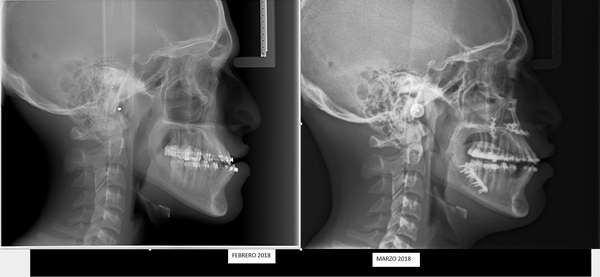

Tratamiento previo y posterior:

La Dra. María Angélica Vila es la ortodoncista de cabecera de Christopher, quien lo comenzó a atender el año 2013, cuando él tenía 10 años. En esa época debió iniciar un tratamiento ortopédico maxilar con una máscara de tracción frontal para tratar de favorecer el crecimiento maxilar, la cual usó durante un año aproximadamente, señala que “por temas de pre y post natal no pude continuar atendiendo a Christopher estando ausente un tiempo del sistema y al volver él ya no estaba en edad para continuar con este tratamiento”.

Por ello, agrega “sólo quedaba la opción de prepararlo para una intervención quirúrgica, la cual en esos momentos no era posible realizarla en el antiguo Hospital Regional, lo que afectó a la familia, ya que en extra sistema tiene un valor aproximado de 12 millones de pesos incluyendo el tratamiento ortodoncico anterior y posterior a la cirugía”.

Vila, destaca que “muchas veces la gente piensa que esto es estético, obviamente que consigo lleva una mejora estética, pero lo importante es que acá se mejora la función del paciente presentando resultados impecables. Una recuperación inicial, que podríamos hablar del postoperatorio, son 15 días, donde se disminuye el edema facial donde él ya puede volver a masticar. Y un mes para que él pueda ya realizar actividad física deportiva y volver a trabajar y a estudiar”.